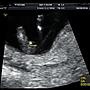

9F→: 醫生告知性別是違法的喔08/09 22:26